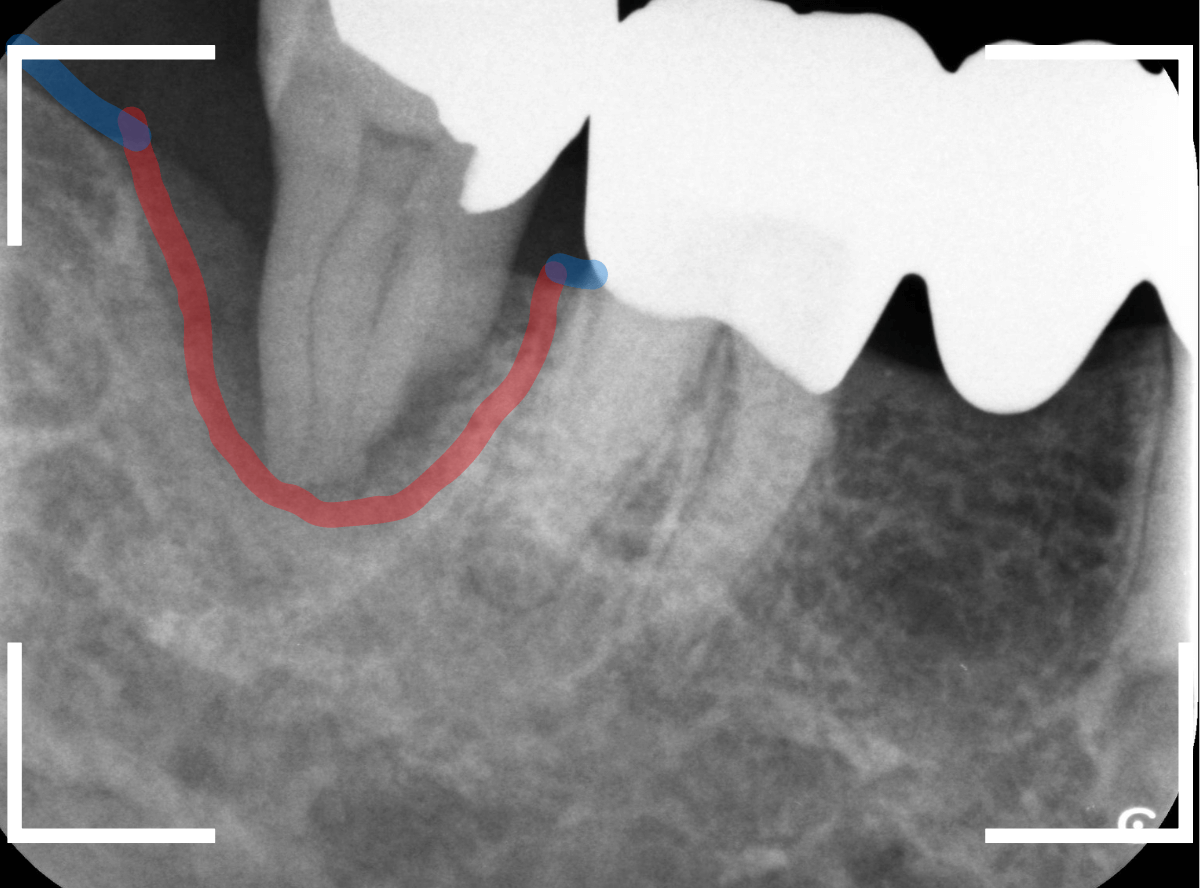

赤いラインが、歯の周りの歯槽骨が部分です。

歯を支える骨がほとんどなく、歯肉の中に埋まっているだけの状態になっています。

残念ながら、この状態では治療で回復する事ができません。

また、無理に残していても、手前の歯の歯周病を進行させる原因になっていまいます。

患者さんに状況をご説明し、抜歯をすることになりました。

こちらが抜歯した歯になります。

今回の歯周病が進行した主な原因は、この歯の根にこびりついた縁下歯石です。

歯の根の先の除去不可能な部分まで、びっしりこびりついていました。

これだけ多くの歯石がたまるには、かなりの期間がかかります。